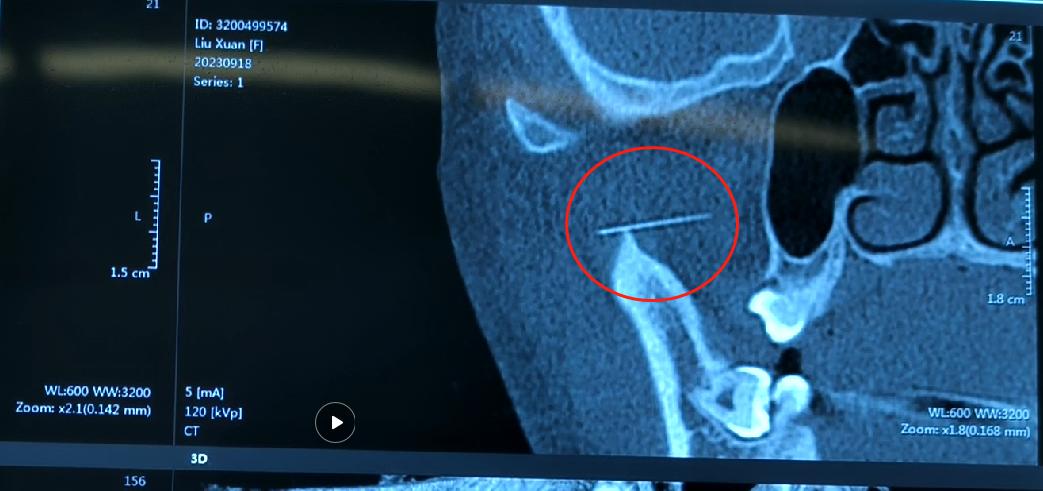

银针断在体内的征兆,银针断针处理 □ 术前影像,红圈内为断针

9月14日,家住内蒙古的笑笑因为身体不适,在母亲的带领下找附近的中医进行针灸治疗,谁也想不到,就是这么一根小小的银针,给这个家庭和笑笑都带来了不可预料麻烦和伤害。

“当时针灸完,拔针的时候发现,针断了,半截针在孩子脸里”,笑笑母亲说到,“当时就赶紧去了我们当地医院,拍了片,医生给我说太小,取不了,让我们去上级医院。”